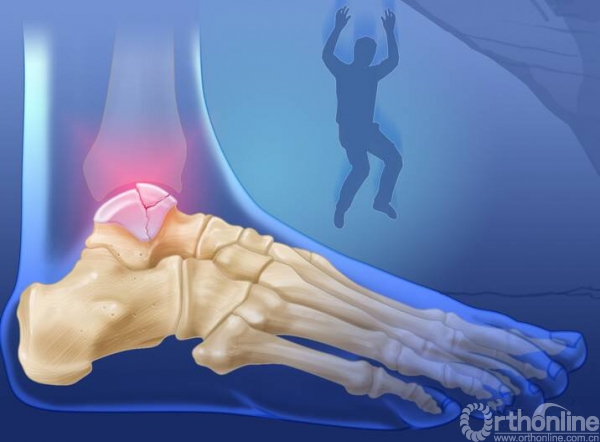

损伤主要位于以下几个主要部分:体、颈、后突、外突

当发生骨折脱位时,由于位移巨大,导致相应位移的血管损伤、最终导致距骨坏死,所以距骨骨折的分型常用Hawkins分型,距骨坏死率随分型严重程度逐渐增加。

1.骨折严重合并脱位的

一定要早期临时外架牵引复位和维持;一定要早期临时外架牵引复位和维持;一定要早期临时外架牵引复位和维持。